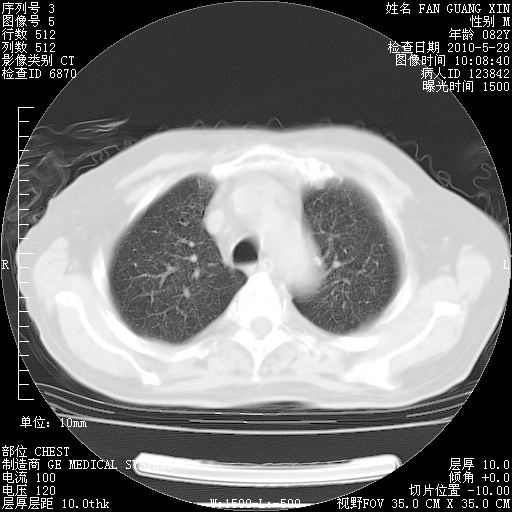

再治疗10天后的肺部CT

从白细胞总数和中性比例看好像合并感染。肺部纹理好像比上次多,支气管炎?其他感染?

阅读此次胸部CT,肺间质渗出性改变较入院时有吸收。目前从体温、白细胞、中性分叶明显增高,肯定存在细菌感染(发生医院感染哦,若无消化道及泌尿系统等感染的依据,肺部感染可能大)。若你院头孢哌酮舒巴坦钠耐药率较高,同意你的方案,若48小时体温仍高,可考虑使用碳青霉稀类抗菌药物,同时可予超声雾化、注意滴数时加大液体量。白蛋白33.30g/L较低哦,需加强营养等支持治疗。